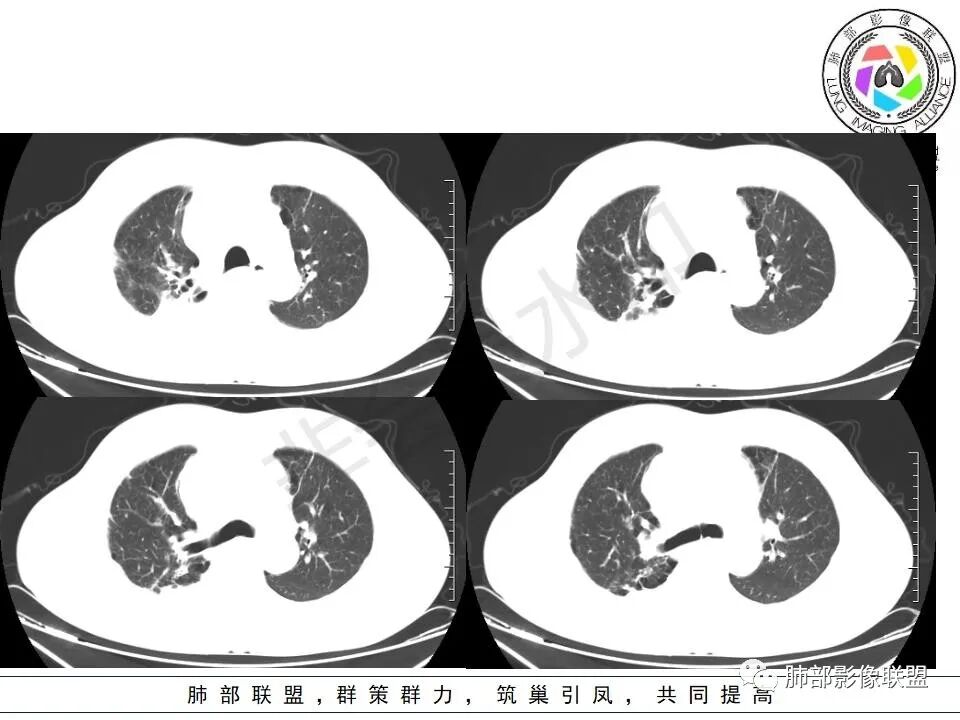

晨读:右肺上叶胸膜下实变影伴有肺大泡(结核?),前纵隔一实性肿块,骑跨主动脉生长,病变侵犯压迫腔静脉,平扫密度均匀,增强扫描均匀强化,内部可见低密度小坏死区无强化,考虑:淋巴瘤,鉴别胸腺癌(坏死偏少)

晨读:男,60岁,面部肿胀一月入院,前纵隔见不规则形实性肿块影,病灶骑跨主动脉生长,部分层面与腔静脉分界欠清晰,增强扫描病灶轻度强化,病灶内见少许坏死,考虑侵袭性胸腺瘤,鉴别淋巴瘤。

晨读:男,60岁,颜面部肿胀1月入院。CT示右肺上叶条索影及实变影伴局部支气管扩张,肺大泡(陈旧性肺结核?)。前纵隔可见实性肿块,骑跨主动脉生长,平扫密度不均匀,内部可见低密度区,增强扫描渐进性不均匀强化,可见坏死区,上腔静脉受侵,考虑为恶性,侵袭性胸腺瘤或胸腺癌>淋巴瘤

晨读病例:男性患者,60岁,面部肿胀一月入院,影像表现,前纵隔实性肿块影,密度均匀,部分层面与腔静脉分界欠清晰,增强扫描病灶轻度强化,病灶内可见低密度无强化区,上腔静脉受侵犯,右侧肺门,纵膈淋巴结增大,考虑恶性病变,胸腺癌>侵袭性胸腺瘤,鉴别淋巴瘤。

2.上纵隔增宽并见不规则块影,密度不均,轻度不均匀强化,隐约见液化密度区。

病灶边界不清,轻度分叶,后方部分紧密包绕升主动脉且侵入上腔静脉及左无名静脉末端,相应上腔静脉及左无名静脉管壁不完整。